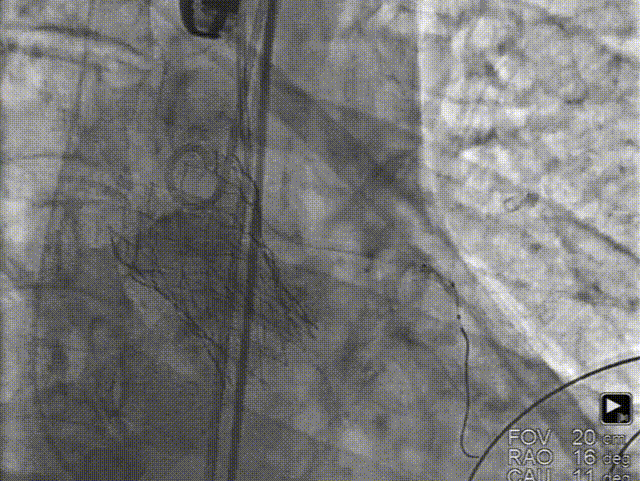

B. 冠脉保护:导丝、球囊、Guidezilla、位于LAD;Guiding回撤至升主动脉适当位置

C. 应用交界贴合技术调整人工瓣膜,标准位释放瓣膜并行释放后造影

• 本例患者原生瓣叶尤其是左冠瓣瓣叶增厚及增长明显,为了进一步降低术中风险,对左冠成功应用冠脉保护技术。同时,通过术前影像分析结合术中评估,在适合的工作角度下,应用Xcor™特有的“极简式”瓣叶交界贴合技术释放瓣膜,为患者未来可能的PCI治疗留下充分的操作空间。术后冠脉血流通畅,撤除冠脉瓣膜,不需要支架植入。